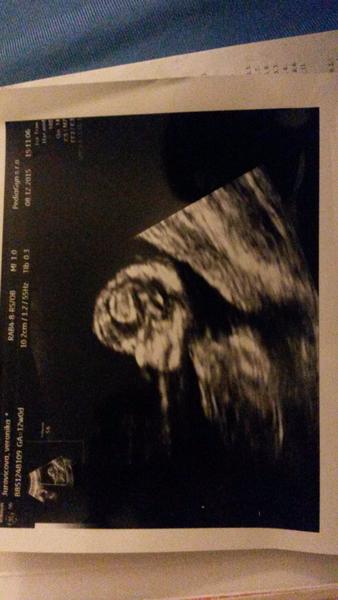

@misella1288 len takto sa mi to da poslat 🙂 drobec malinky 🙂